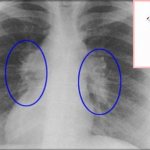

• Визуализирующие методы (МРТ, КТ, УЗИ). Они помогают выявить сплено-, гепатомегалию, дегенерацию базальных ганглиев (головной мозг).